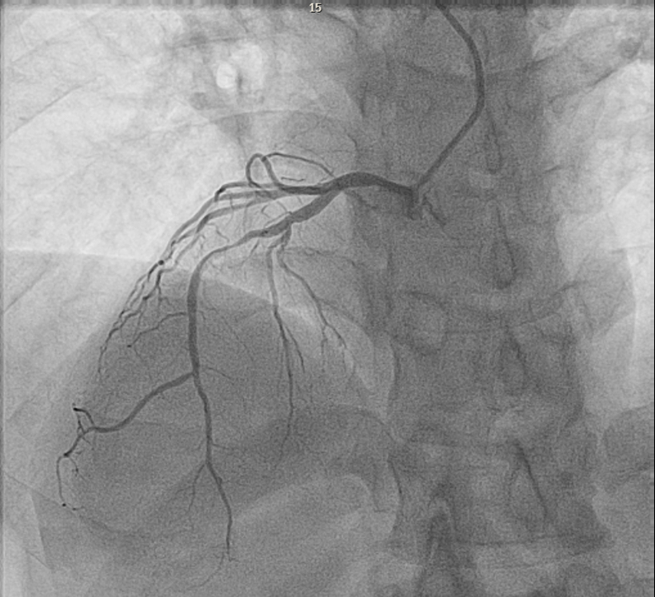

A coronary angiogram from the right radial with a 6 French Tiger Radial Catheter in the right anterior projection (RAO) 30 degrees showed minor luminal irregularities in the RCA, and 90% stenosis in the LAD. RCA was enganged anticlockwise and LCA clockwise.

A 6 French XB 3.5 guide catheter was used to engage the LCA system, and the mid-LAD was stented. DAPT including Aspirin and Ticagrelor, was initiated. A TTE showed an EF of 25-30% with severe anterior, apical, and septal wall hypokinesis. The patient was discharged home with GDMT for coronary artery disease.

Engaging the coronary arteries is challenging. We used a Tiger radial catheter with a reverse torque technique: anticlockwise for the RCA and clockwise for the LCA. Both arteries were engaged in the right anterior oblique view at 30 degrees. The cranial and caudal angulation remained the same, but the standard left anterior oblique view was switched with the right anterior oblique view and vice versa. The double inversion technique is useful during interventions when dealing with unfamiliar anatomy. It is not well-established whether dextrocardia is a risk factor for myocardial infarction.